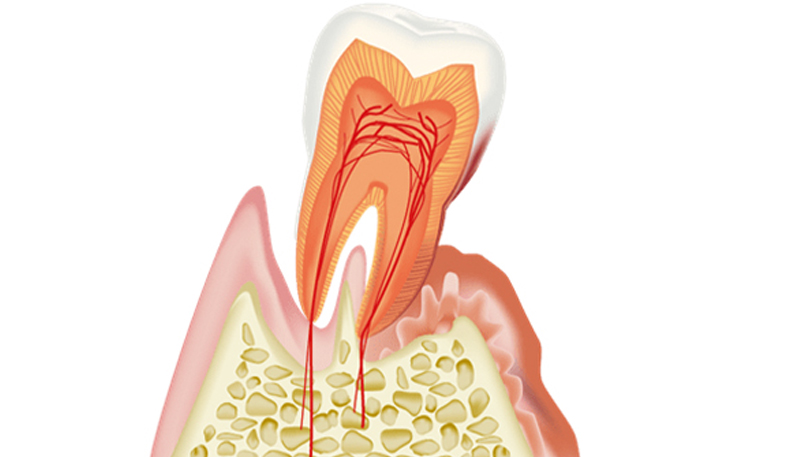

- 歯周病とは

歯肉炎の状態が続く事で、細菌が増えて歯を支える骨が溶けていく病態を言います。

細菌が骨を溶かしているのではなく、細菌に対する私たちの身体の免疫反応の結果骨が溶けていきます。

虫歯のような痛みが出にくいので、定期的な検査とメンテナンスが大切です。

歯肉炎・歯周病になる原因

全ての人は健康な歯茎からスタートします。 健康な歯茎に細菌性のプラーク(汚れ)が溜まると歯肉炎になります。 歯肉炎はプラークが溜まれば全ての人がなります。 ところが歯肉炎の状態からさらにプラークが溜まっても、歯周病になる人とならない人がいます。 これには宿主反応(個人の免疫力)が大きく関係しています。 汚れがいっぱいついていても歯周病にならない人もいれば、汚れが少量しかついていないのに歯周病が進行してしまう人がいるのはこのためです。 歯肉炎=プラークですが、歯周病=プラーク+宿主反応です。 タバコ、糖尿病、生活習慣病などが歯周病を悪化させる修飾因子となります。

歯周病が原因で抜歯を選択せざるを得ないケースは少なくありません。 歯周病が進行すると、歯と歯肉の間に深い隙間(ポケット)が形成され、そこで細菌が増殖しさらに歯周病を悪化させるという悪循環が生じます。さらに細菌が産生する毒素や、それが原因となる炎症に起因して歯を支える骨も溶けてしまいます。 一般的に、歯周ポケットが6mmを超える状態、また、レントゲン上で歯を支える骨の吸収が大きい場合(歯根の1/3以上)、またそれにより歯のぐらつきが大きい場合は抜歯を考慮しなければなりません。